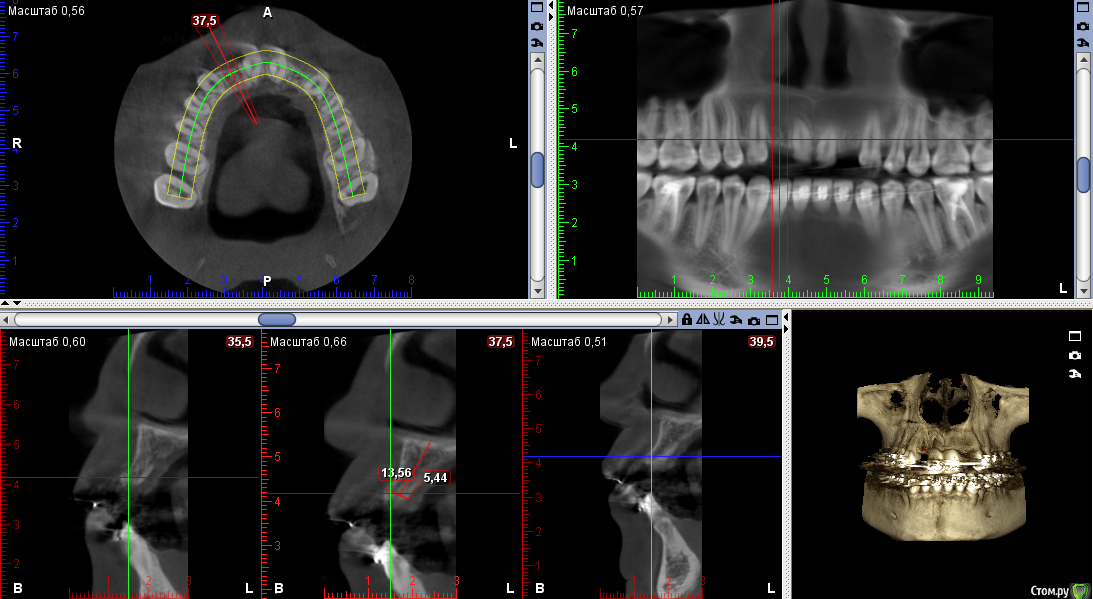

Тимур86 Опубликовано 22 сентября, 2016 Поделиться Опубликовано 22 сентября, 2016 Пациентка на ортодонтическом лечении.Нуждается в имплантации 12,22.В другой клинике предложили удалить 11 и 21 с костной пластикой,т.к. вестибулярно в области 11 отсутствует кость....Планируется установка Astra 3.0 в области 12 и 22 с использованием хирургического шабона,подсадкой СДТ и установкой ФДМ,через неделю временные коронки.Вопросы:1)зачем удалять 11 и 21? 2)нужна ли НКР? 3)можно ставить времяшки через неделю,учитывая подсадку СДТ? Ссылка на комментарий

колесников Опубликовано 22 сентября, 2016 Поделиться Опубликовано 22 сентября, 2016 Бред какой-то. Судя по снимку нет оснований ни для удаления,ни для нкр(с натяжкой 12),возможно визуально иначе. Поставил бы 3.5х9 ,сст и нагрузка. 2 Ссылка на комментарий